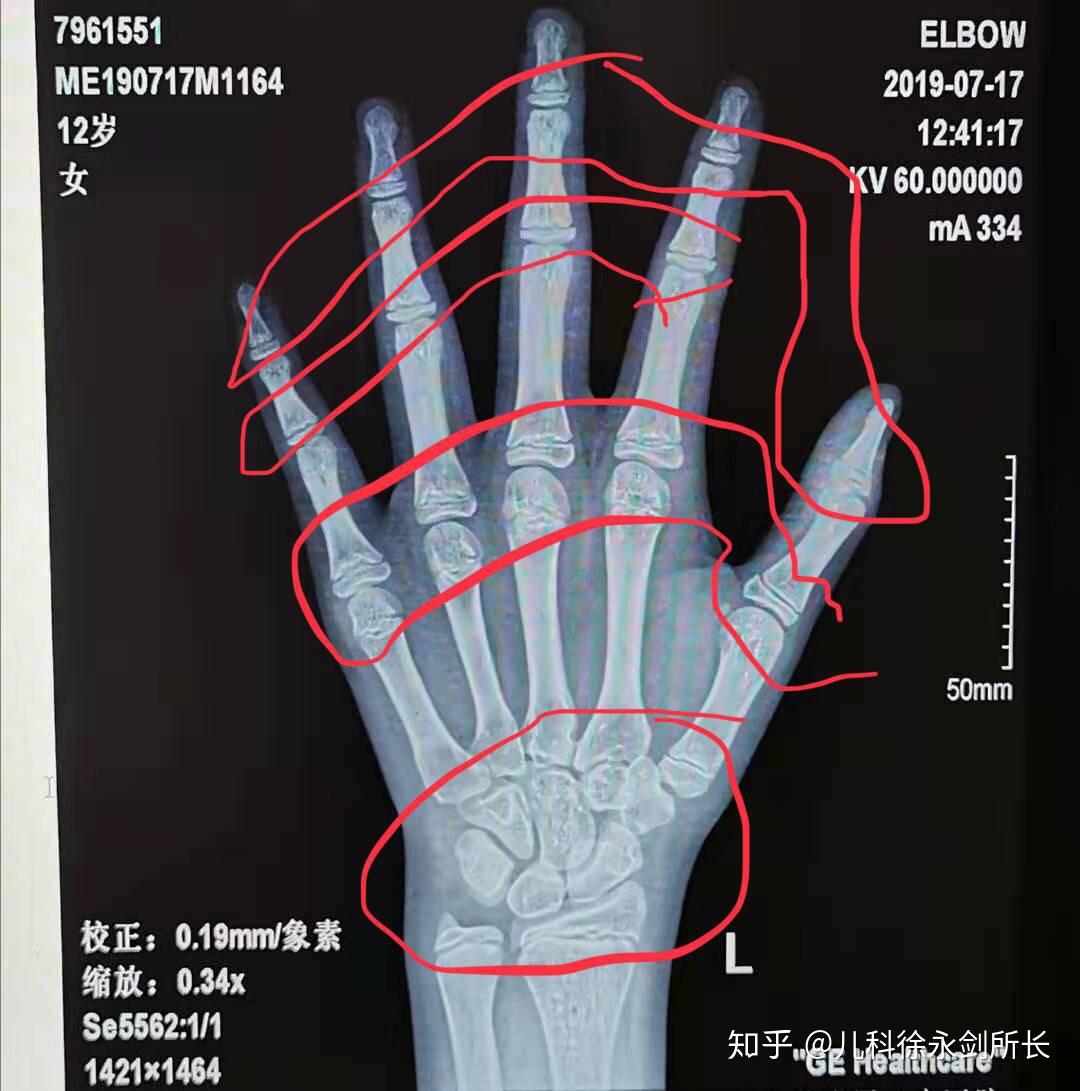

生长发育科徐永剑所长

鉴定分析:中华05标准鉴定数据为14.2岁骨龄.